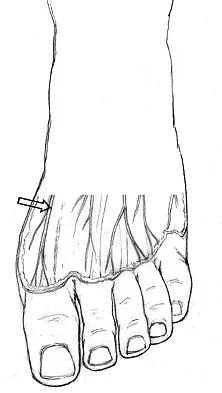

The orthosis shown in Figure 47 is commonly used for

Explanation